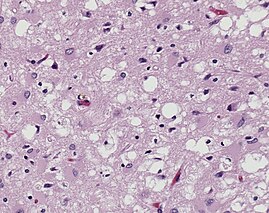

Magnified 100X and stained. This photomicrograph of the brain tissue shows the presence of the prominent spongiotic changes in the cortex, with the loss of neurons in a case of a variant of Creutzfeldt-Jakob disease (vCJD)

Prions are misfolded proteins that are transmissible and can influence abnormal folding of normal proteins in the brain. They do not contain any DNA or RNA and cannot replicate other than to convert already existing normal proteins to the misfolded state. These abnormally folded proteins are found characteristically in many neurodegenerative diseases as they aggregate the central nervous system and create plaques that damages the tissue structure. This essentially creates "holes" in the tissue. It has been found that prions transmit three ways: obtained, familial, and sporadic. It has also been found that plants play the role of vector for prions. There are eight different diseases that affect mammals that are caused by prions such as scrapie, bovine spongiform encephalopathy (mad cow disease) and Feline spongiform encephalopathy (FSE). There are also ten diseases that affect humans such as, Creutzfeldt–Jakob disease (CJD).[29] and Fatal familial insomnia (FFI).